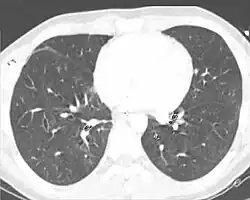

Computed tomography

Computed tomography (CT scanning) is a more sensitive test for pulmonary contusion,[8][38] and it can identify abdominal, chest, or other injuries that accompany the contusion.[43] In one study, chest X-ray detected pulmonary contusions in 16.3% of people with serious blunt trauma, while CT detected them in 31.2% of the same people.[50] Unlike X-ray, CT scanning can detect the contusion almost immediately after the injury.[48] However, in both X-ray and CT a contusion may become more visible over the first 24–48 hours after trauma as bleeding and edema into lung tissues progress.[51] CT scanning also helps determine the size of a contusion, which is useful in determining whether a patient needs mechanical ventilation; a larger volume of contused lung on CT scan is associated with an increased likelihood that ventilation will be needed.[48] CT scans also help differentiate between contusion and pulmonary hematoma, which may be difficult to tell apart otherwise.[52] However, pulmonary contusions that are visible on CT but not chest X-ray are usually not severe enough to affect outcome or treatment.[42]